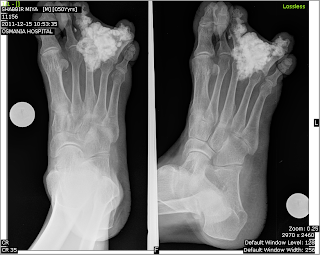

Present x ray

4 months back xray